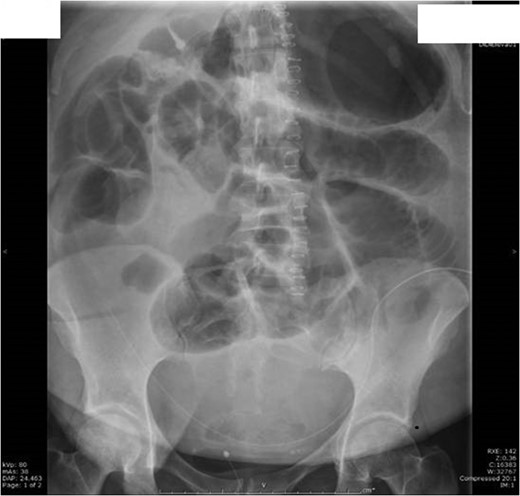

On Day 1 post surgery she was noted to be tachycardic, febrile and hypertensive with a drop in saturation 92–93% on room air along with abdominal pain. Her differential diagnosis included atelactesis, pulmonary embolism and endometriosis (Fig. 1). On examination she had good bowel sounds, was passing flatus but had not opened her bowels. On Day 2 she had localized right lower quadrant tenderness with raised inflammatory markers of CRP 163, WCC 21 × 109/l and neutrophil count 17 × 109/l. The computed tomography (CT) scan of her abdomen/pelvis (A/P) showed evidence of ileus with dilated loops of bowel (Fig. 2).

Day 2 post op CT A/P with no evidence of intra-abdominal collection/foreign body. Dilatation of entire intestine (large bowel up to 9 cm) most likely representing postsurgical ileus rather than a mechanical obstruction.